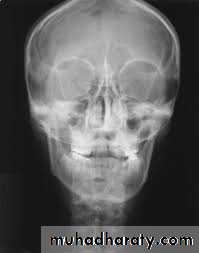

Orthopantomogram

This is essential in all trauma cases where underlying bony injury is suspected.